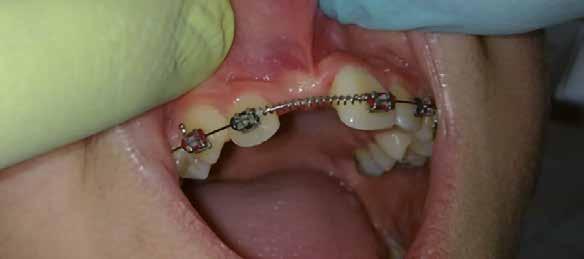

A szemfog elcsiszolásához piros gyémántfúró javasolt, finom szemcsézettséggel, 27-76 µm (okkluzálisan lekerekített – Rodentica, speciális hegyű 806314466514031, Komet 8833), gyorsítóval (max 160 000 fordulat/perc) megfelelő hűtés mellett, legalább 50 ml/perc. Ezt követi a felület kidolgozása és polírozása sárga gyémántcsiszolóval, extra finom szemcsézettséggel, 10-36 µm (Rodentica 806314466504031) és narancssárga Sof-Lex korongokkal (finom alumínium-oxid szemcsék 3-40 µm, extra finom, narancssárga-sárga, alumínium-oxid kristályok mérete 1,7 µm) könyökdarabban (25000 fordulat/perc) megfelelő hűtés mellett min. 50 ml/perc (2. a-d. ábra).

A szemfog megfelelő inklinációjának eléréséhez az oldalsó metsző helyén a palatinális felszínt is el kell csiszolni. Ennek a felületnek nem szabad interferenciát okoznia a harapásban, és lehetővé kell tennie a megfelelő metszőfog-vezetést [14]. A formázás előtt meg kell vizsgálni a szemfog vesztibulo-orális pozícióját. Lapos vesztibuláris felszínnel rendelkező szemfog esetén szükség lehet egy elsőrendű hajlításra a középső metsző és szemfog között (főleg, ha a szemfogon egy oldalsó metsző bracket van, melyben a beépített in-out érték magasabb) annak érdekében, hogy elérjük a megfelelő vesztibulo-orális pozíciót a fognyak szintjén, és elkerüljük a palatinális elcsiszolást (3. a-b ábra), [39].

3. a–b ábra: .019x.025” acél mint befejező fogszabályozóív vesztibuláris hajlításokkal a 11-13., a 21-23., valamint a 24-25. és a 14-15. fogak között. 4. a-b. ábra: A szemfog palatinális felületének formázása (a, Rodentica 257) és polírozása narancssárga Sof-Lex koronggal (b). A braketeket már eltávolították ezekről a fogakról.